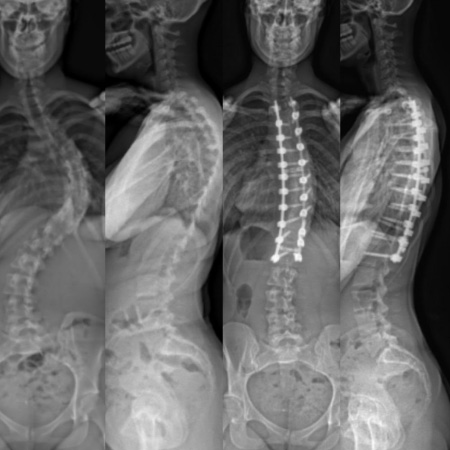

Surgery is generally reserved for the severe cases where non-surgical treatments are not appropriate. Kyphosis surgery is a major spinal surgery with the goal of stabilizing a kyphosis that is worsening over time.